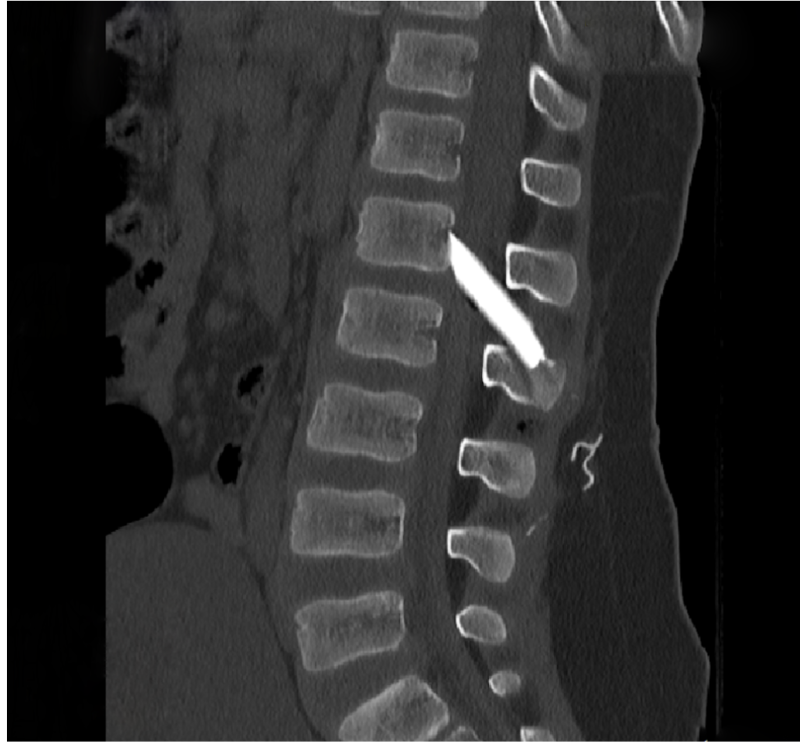

Οι μαγνητικές και αξονικές τομογραφίες πραγματοποιήθηκαν άμεσα, επιβεβαιώνοντας τις αρχικές υποψίες: δύο μεγάλα κομμάτια γυαλιού είχαν ενσφηνωθεί στη σπονδυλική στήλη, εισχωρώντας εντός του σπονδυλικού σωλήνα σχίζοντας την ιππουρίδα και την μήνιγγα που την περιβάλλει.

Ακολούθησε άμεση εισαγωγή του παιδιού στο χειρουργείο, όπου με πολύ προσεκτικούς χειρισμούς και τη χρήση προηγμένου εξοπλισμού, όπως το σύστημα χειρουργικής πλοήγησης, πραγματοποιήθηκε επιτυχής αφαίρεση όλων των κομματιών γυαλιού μετά από ένα πολύωρο και απαιτητικό χειρουργείο.